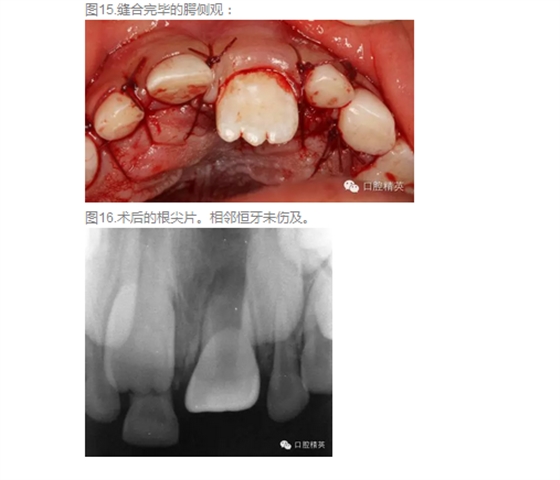

首頁口腔外科 高難度含多生牙囊腫的摘除

高難度含多生牙囊腫的摘除